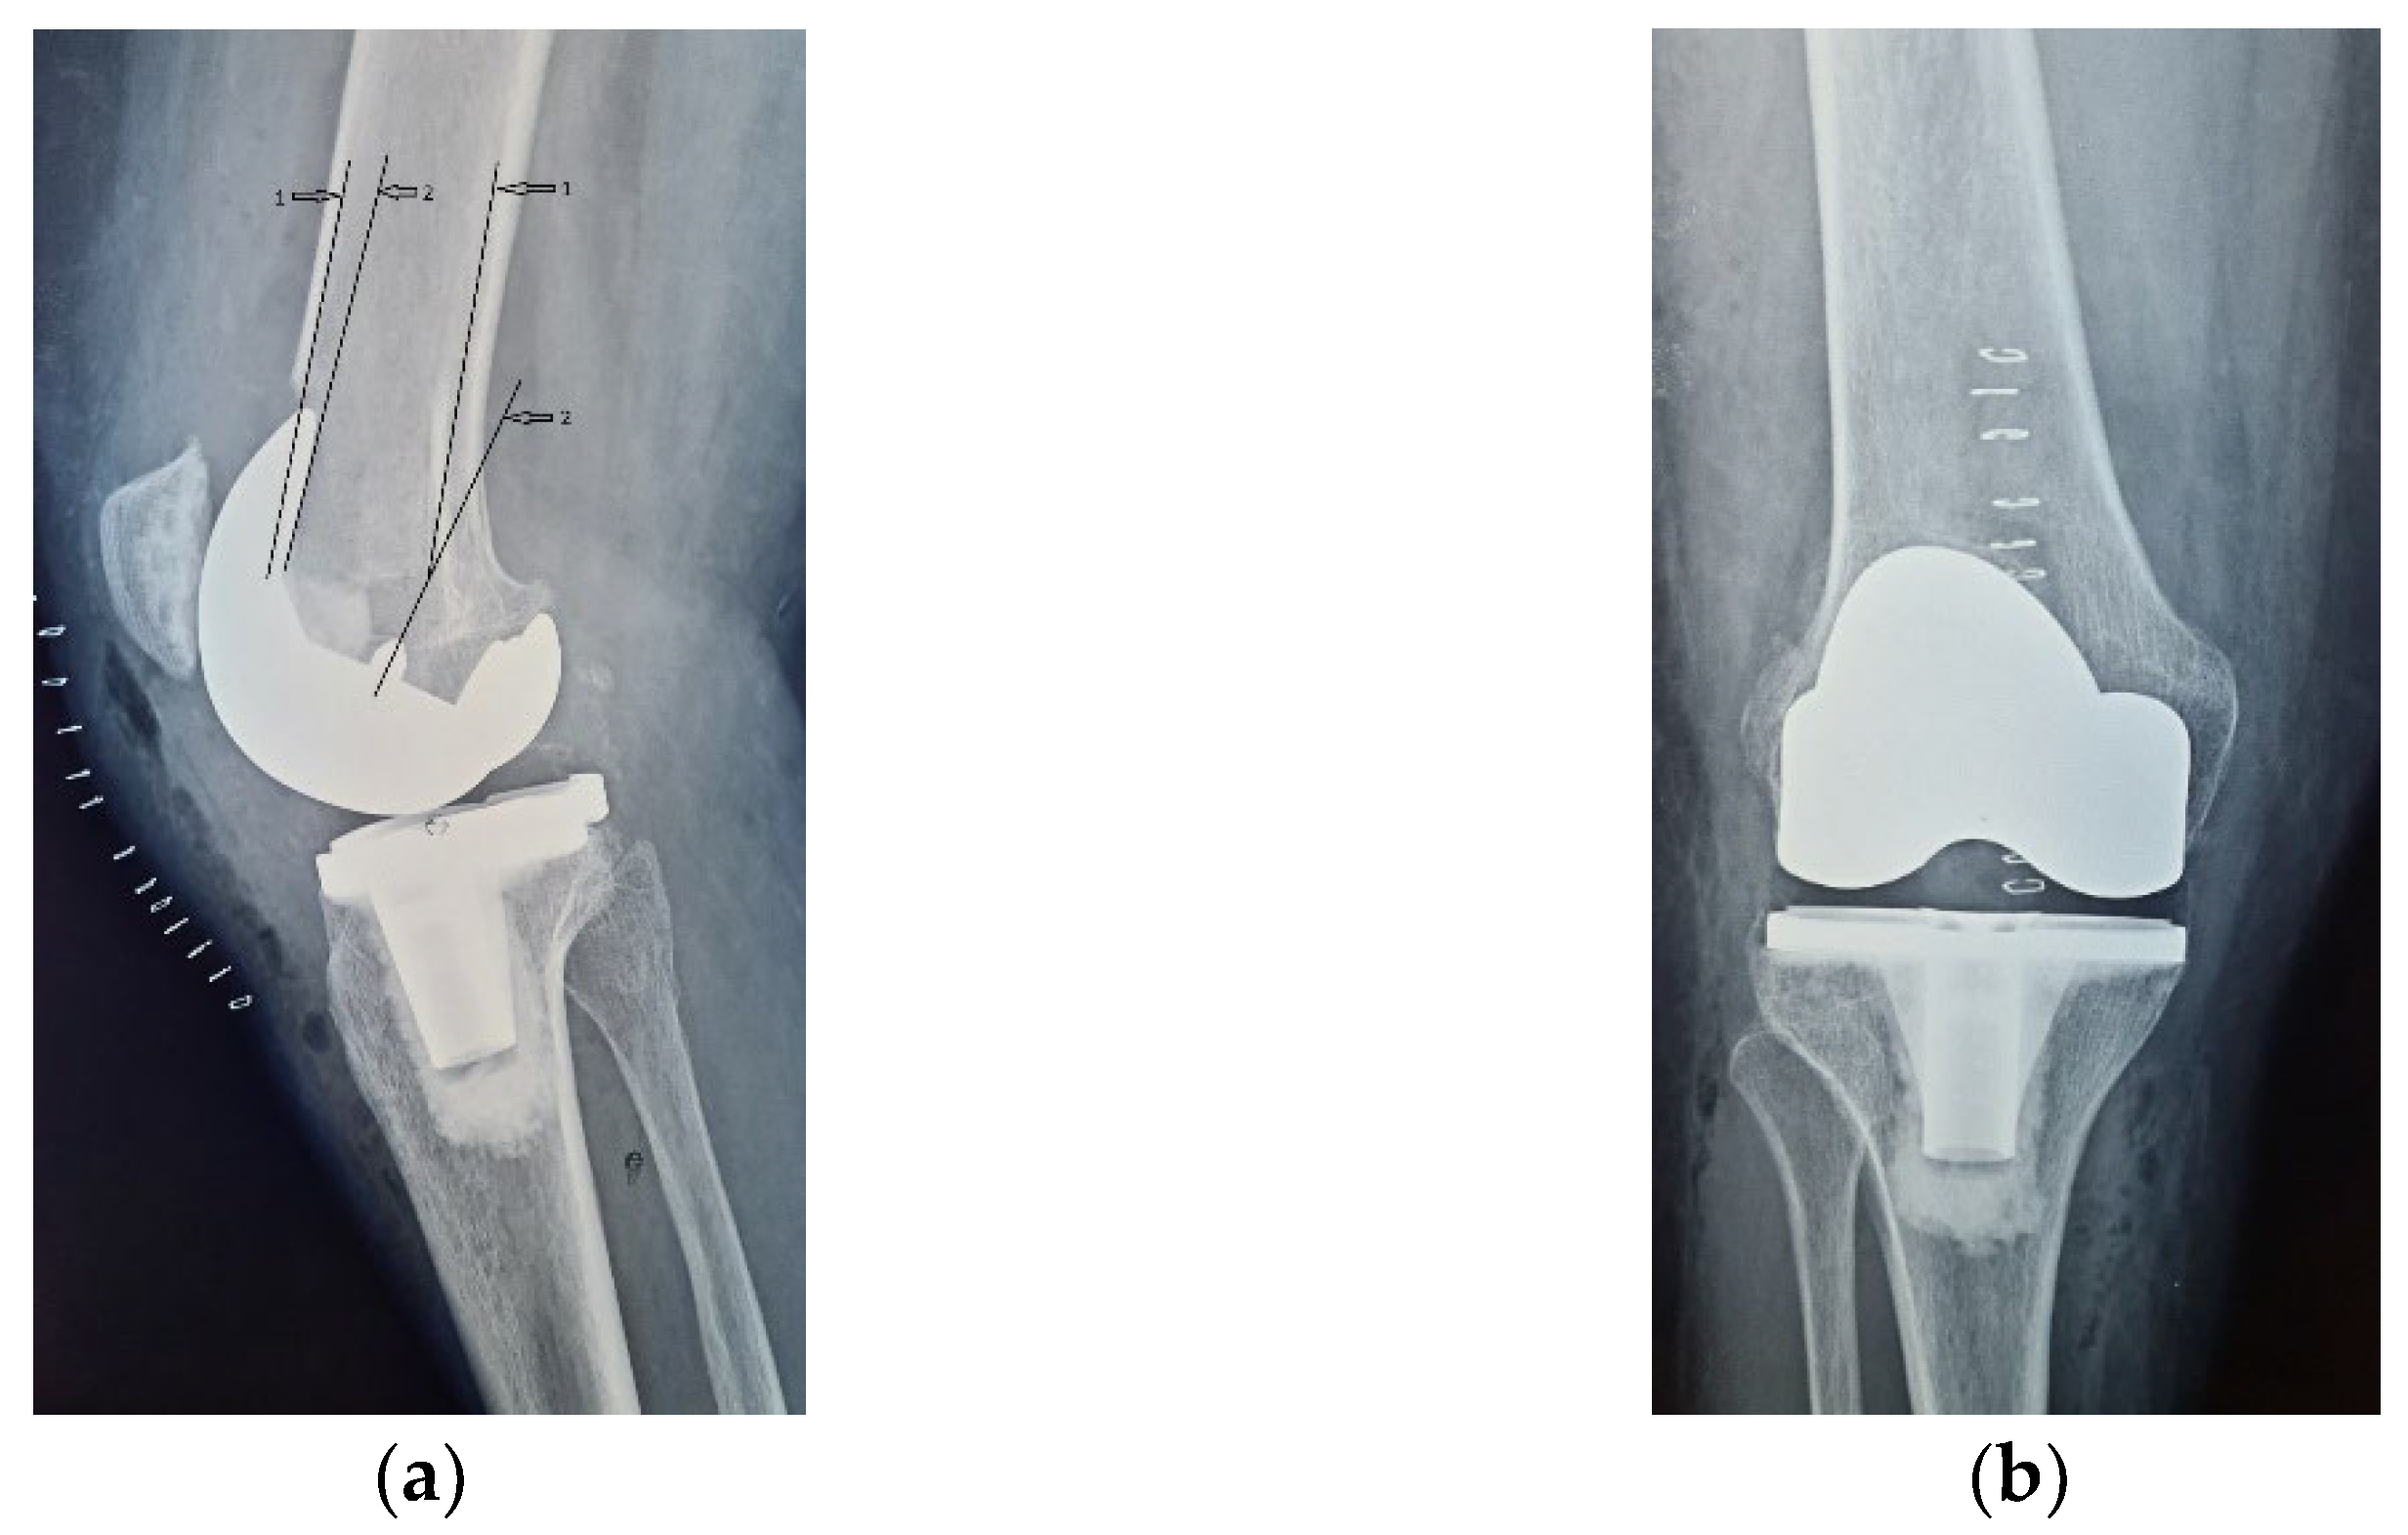

Four years ago, the patient was diagnosed with Ahlback stage IV gonarthrosis and underwent a simultaneous bilateral TKA surgery in another orthopedic clinic. Two NexGen cemented total prostheses were then implanted, with patellar resurfacing performed only on the right side, due to anesthetic complications which required a drastic shortening of the operating time, thus preventing the surgical team from performing resurfacing on the contralateral patella. Although postoperative radiological images showed a slight implantation error in the femoral component on the right side, extensive anterior resection with posterior rotation of the femoral component, the clinical outcome was satisfactory (Figure 1).

Figure 1.

Right knee, initial after surgery radiological image: (a) lateral view, extensive anterior resection, femoral posterior rotation, femoral component axis intersecting diaphyseal axis at a 15.4° angle with (1) marking the femoral diaphyseal axis and (2) marking femoral component rotation axis; (b) coronal view.

On the other hand, on the left side, where patellar resurfacing was not performed, although the radiological images show a satisfactory implantation of the prosthesis with correct alignment of the tibial and femoral components, but with slight subluxation of the patella, the clinical evolution was unsatisfactory (Figure 2). Shortly after operation, 3–4 weeks, the patient experienced discomfort, pain and swelling of the left knee.

Figure 2.

Initial radiological aspect of the left knee, right after surgery: (a) lateral view, femoral component axis parallel with femoral diaphyseal axis; (b) coronal view, slight lateral patellar subluxation (arrow) compared to femoral axis with (1) marking the femoral trochlear axis, (2) the patellar axis, and (3) patella must be centered in the femoral trochlea.